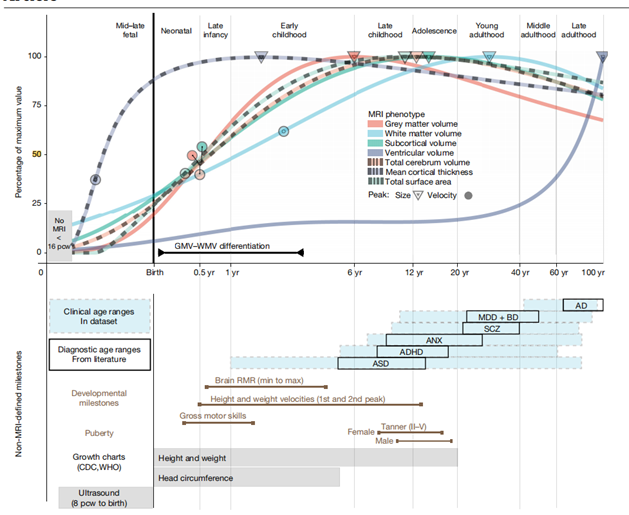

灰质在青春期前达到峰值,皮质下灰质在青春期中期达到峰值,白质在成年早期达到峰值(如图3所示)。灰质,皮质下灰质,白质的增长速度都在婴儿期和儿童早期达到峰值。大脑总体积的增长速度在灰质和白质的最大速度之间,大脑总体积的增长速度大约在7个月时达到峰值。大脑总体积和皮质下灰质体积的两个主要里程碑(速度峰值和大小)(如图3所示)与新生儿和青少年的身高和体重的变化速度相吻合。平均皮质厚度的速度更早地达到了峰值,在产前时期的-0.38岁(相对于出生),大约对应于妊娠中期。

图3:神经发育里程碑